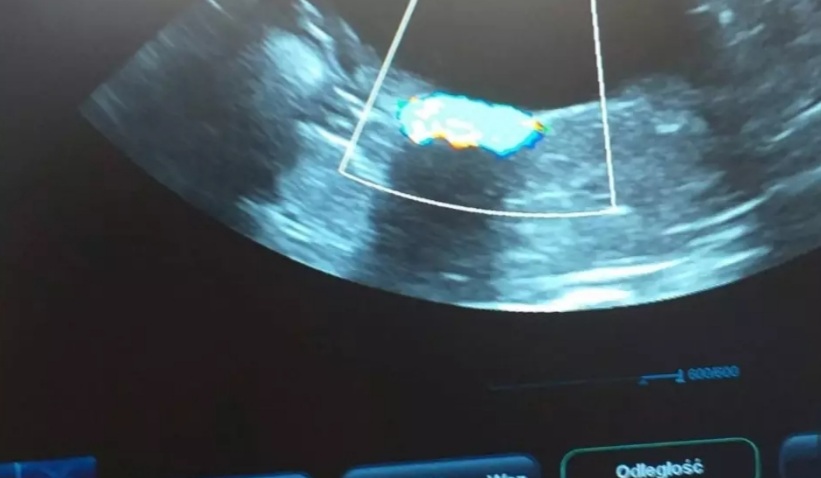

Gdyby nie Mikuś, nie prosiłabym Was o pomoc, ale on jest naszym słoneczkiem i chcemy mu pomóc. Post będzie długi, ale będę wdzięczna za przeczytanie. Mam na imię Karolina, mamy z chłopakiem trzy koty i psa. Ze względu na stan zdrowia pracuję w sklepie na pół etatu, mój chłopak w czasie koronawirusa został zwolniony, szuka pracy i pracuje dorywczo na czarno. Dotychczas jakoś sobie radziliśmy, było skromnie, ale byliśmy razem i mieliśmy cudowne zwierzaki. W styczniu nasz kocurek Mikuś zaczął chorować pojawił się krwiomocz, problemy z wypróżnianiem, pozycja bólowa, napięty brzuch. Pojechaliśmy do weterynarza i okazało się, że Mikuś ma w moczu mnóstwo kryształków struwitów i całkowicie zatkane jelita :( Został w klinice, poddano go narkozie, zrobiono lewatywę, badania moczu, dostał zastrzyki przeciwbólowe, rozkurczowe, antybiotyki, kapsułki na rozcieńczenie moczu i zalecenie karmienia dobrą mokrą karmą. Zapłaciliśmy 350 zł, później dodatkowo dokupiliśmy kapsułki za 65 zł, do tego karma urinary. To był dla nas ogromny strzał finansowy, bo dotychczas wystarczyło nam na opłatę mieszkania, rachunków i bardzo skromne jedzenie dla nas i zwierząt (a właściwie głównie dla nas, bo często woleliśmy kupić coś lepszego zwierzakom niż sobie). Niestety problemy Mikusia nawracały. Każda wizyta u lekarza to koszt 150-200 zł. Kolejne kapsułki, kolejna karma specjalistyczna i powoli zaczęliśmy się załamywać, czy damy radę temu sprostać finansowo.